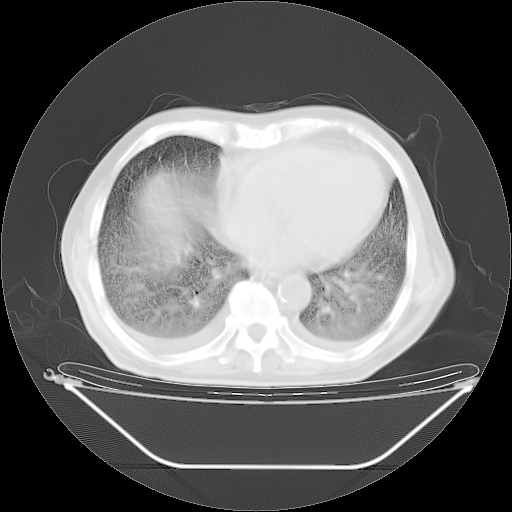

今天复查肺部CT,发现双肺广泛磨玻璃样改变。所以我把3月19日和5月9日相隔50天的肺部CT上传。请大家会诊。

5月9日肺部CT(在4月27日齐鲁医院肺部CT描述部分肺组织磨玻璃样改变,12天后肺组织广泛磨玻璃样改变)

2009年5月9日肺部CT

大致读了系列胸部CT:纵隔窗无明显异常,肺窗:从4、27至今:主要是双肺中下野外带可见毛玻璃样改变,目前处于急性肺泡炎阶段,至于原因考虑1、结替组织或胶原血管性疾病所致?2、恶性疾病如恶组在肺部所致的表现或细支气管肺泡癌?3、药物或其它原因如肺蛋白沉着症所致肺泡炎目前不太可能?总之,明天就去请我院的呼吸科、感染科、血液科和临免专家会诊哈。